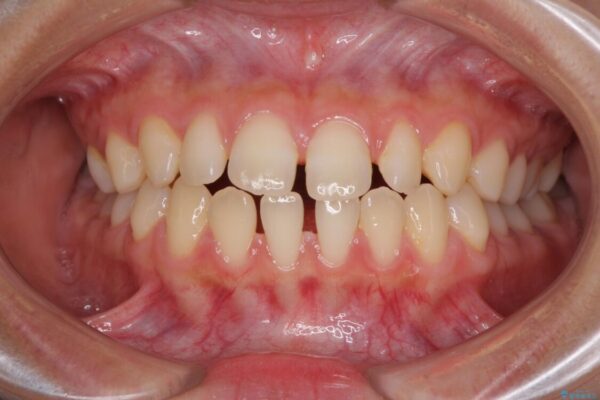

前歯の上下スペースと前歯の隙間を気にして来院された患者様です。

治療前

• 隙間だらけの歯列 インビザラインで改善 治療前画像